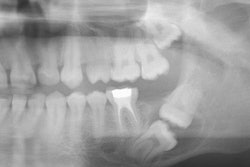

The study analyzed 1,000 CBCT scans from 500 men and 500 women, examining a total of 2,000 maxillary sinuses. Both sinuses were reviewed for each patient, even if only one side required an implant. Panoramic radiographs provided an initial overview of the posterior maxilla followed by detailed coronal and sagittal CBCT reconstructions for thorough sinus evaluation, Küçükkurt wrote.